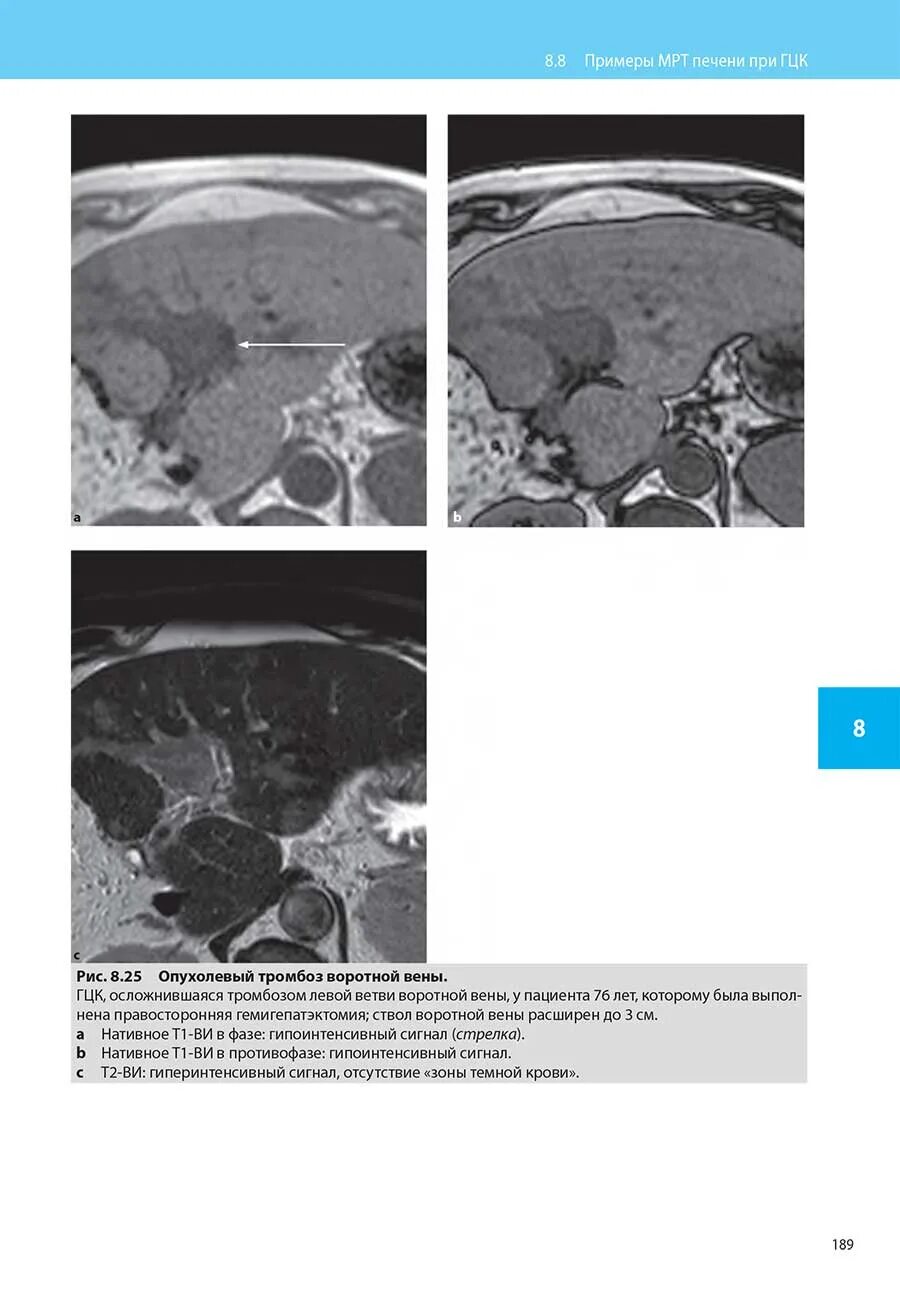

Подготовка к мрт печени